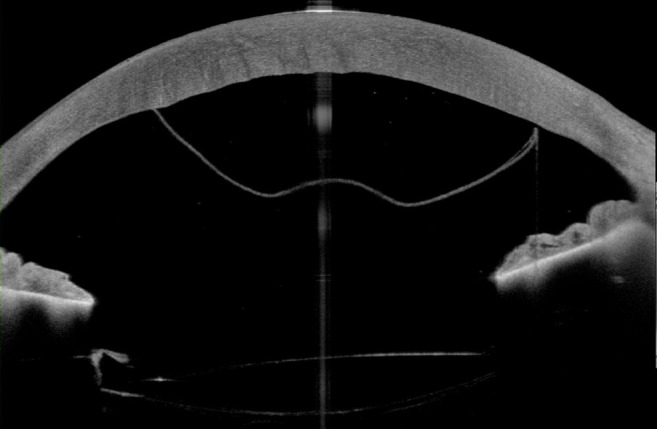

Case presentation: A 71-year-old patient presented after complicated cataract surgery with decreased visual acuity and cloudy vision. On examination, best corrected visual acuity was 1.5 logMAR. A high-resolution swept-source OCT (Anterion, Heidelberg Engineering, Heidelberg, Germany) was used to better evaluate and visualize the extent of DMD. An anterior chamber gas bubble was injected to reattach the Descemet membrane (DM) to the corneal stroma. The success of the surgery was visualized using the high-resolution swept-source OCT. This revealed a completely attached Descemet membrane.

Conclusions: Clinically, it can be difficult to distinguish the etiology of epithelial and stromal edema post cataract surgery. This case demonstrated the clinical usefulness using high resolution swept source imaging to guide clinical decision making in evaluating timing and treatment success of pneumodescemetopexy after complicated cataract surgery.